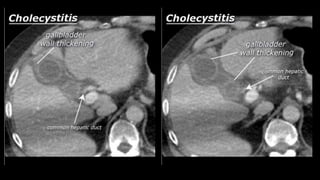

• Gallbladder and bile ducts

• Normal undilated intrahepatic bile ducts are

invisible on an abdominal CT.

• The left and right hepatic duct join to form the

common hepatic duct. These in turn join the

cystic duct to form the choledochous duct. The

choledochous duct eventually joins the

pancreatic duct at the level of Vater's papilla,

where the bile and pancreatic juice is released

into the duodenum (fig. 11).

• The choledochous duct is frequently

identifiable on CT scans; it should be < 6 mm.

• Cholecystitis • Acomplication of bile stones is an infected gallbladder or cholecystitis. Cholecystitis rarely occurs in the absence of bile stones. Ultrasound is also best suited to diagnose cholecystitis. Ultrasound improves the visibility of the bile stones, and gallbladder compressibility can be evaluated (dynamic examination). Absent compressibility constitutes a key characteristic of cholecystitis (see abdominal ultrasound class). Other characteristics of cholecystitis on CT include gallbladder wall thickening and infiltration of the fat surrounding the gallbladder. A common complication of cholecystitis is gallbladder perforation, where bile leaks into the abdominal cavity (biloma).